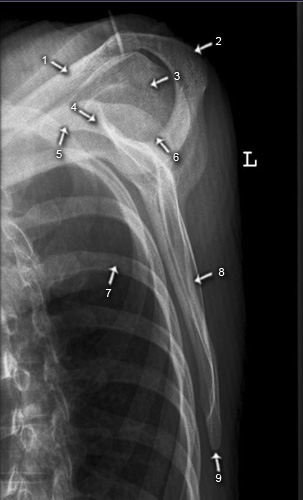

Schulter seitlich (Y-View)

1. Clavicula

2. Articulatio acromioclavicularis (AC-Gelenk)

3. Acromion

4. Caput humeri

5. Cavitas glenoidalis

6. Scapula

7. Humerus

8. Processus coracoideus

9. Angulus superior scapulae